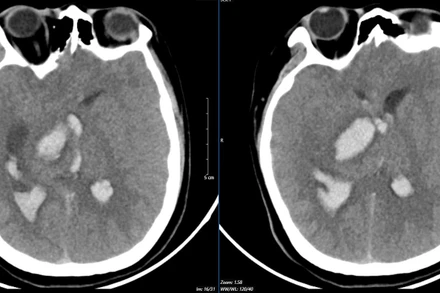

Bác sĩ cảnh báo tình trạng dị dạng mạch máu não từ những triệu chứng thường xuyên bị đau đầu, đột ngột nói khó, giảm thị lực, tê hoặc yếu tay chân,…